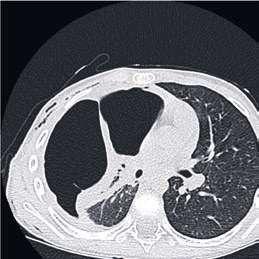

60 Akútne respiračné zlyhanie

MUDr. Ivana Gondová, PhD.